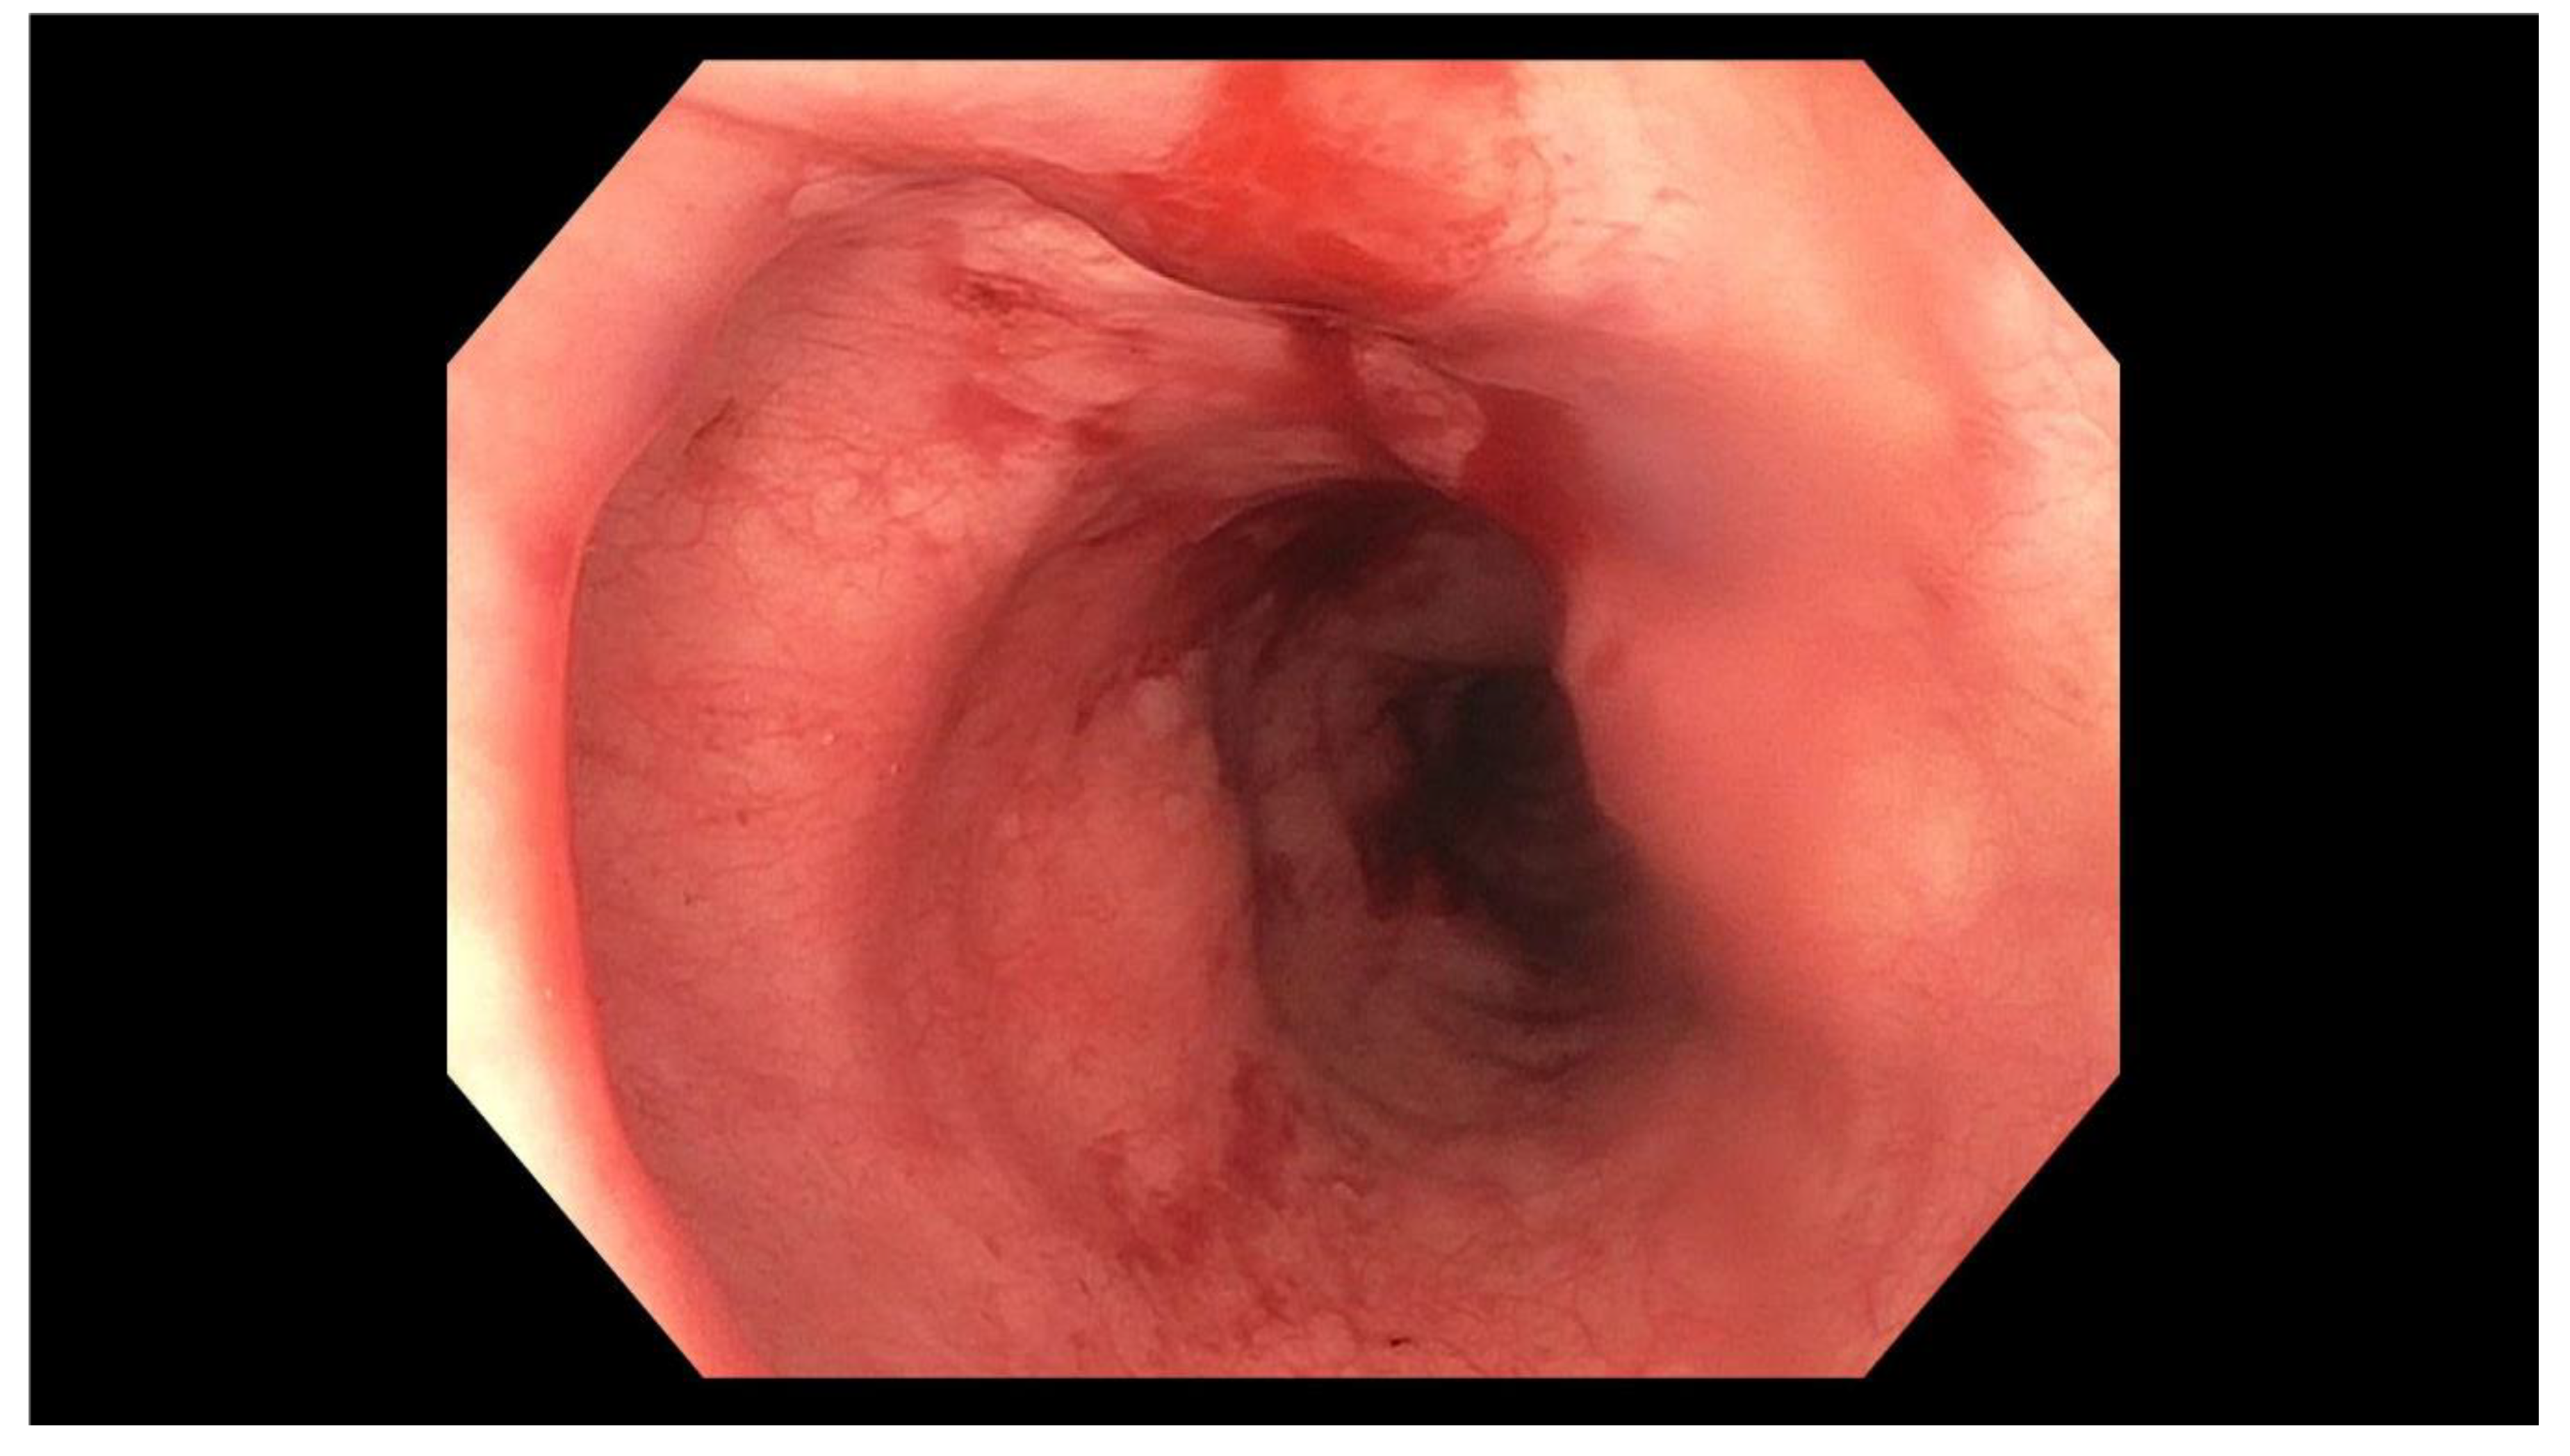

2. Case Report